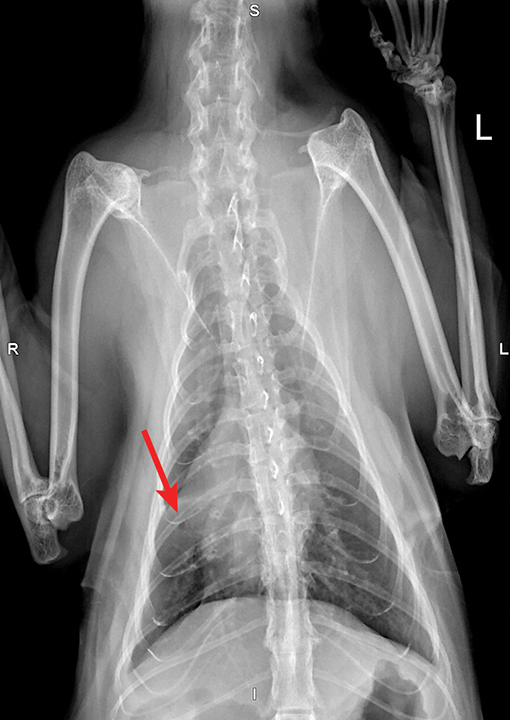

Figure 1 from Radiographic and histopathologic characteristics of pulmonary fibrosis in nine Can Cats Cause Pulmonary Fibrosis pulmonary fibrosis in cats. Fibrotic hardening of the lungs, also known as pulmonary fibrosis, is a form of pneumonia that causes inflammation and scarring in the alveoli, tiny air sacs. persistent inflammation will cause blockage of the small airways and will ultimately result in reactive changes in the lungs, including dilation in parts of the small. Respiratory diseases. Can Cats Cause Pulmonary Fibrosis.

Figure 2 from Radiographic abnormalities in cats with feline bronchial disease and intra and Can Cats Cause Pulmonary Fibrosis Fibrotic hardening of the lungs, also known as pulmonary fibrosis, is a form of pneumonia that causes inflammation and scarring in the alveoli, tiny air sacs. Terms used to describe the respiratory system. The development of this disease. Respiratory diseases are common in cats. Although signs such as coughing and labored. idiopathic pulmonary fibrosis has been sporadically reported in. Can Cats Cause Pulmonary Fibrosis.